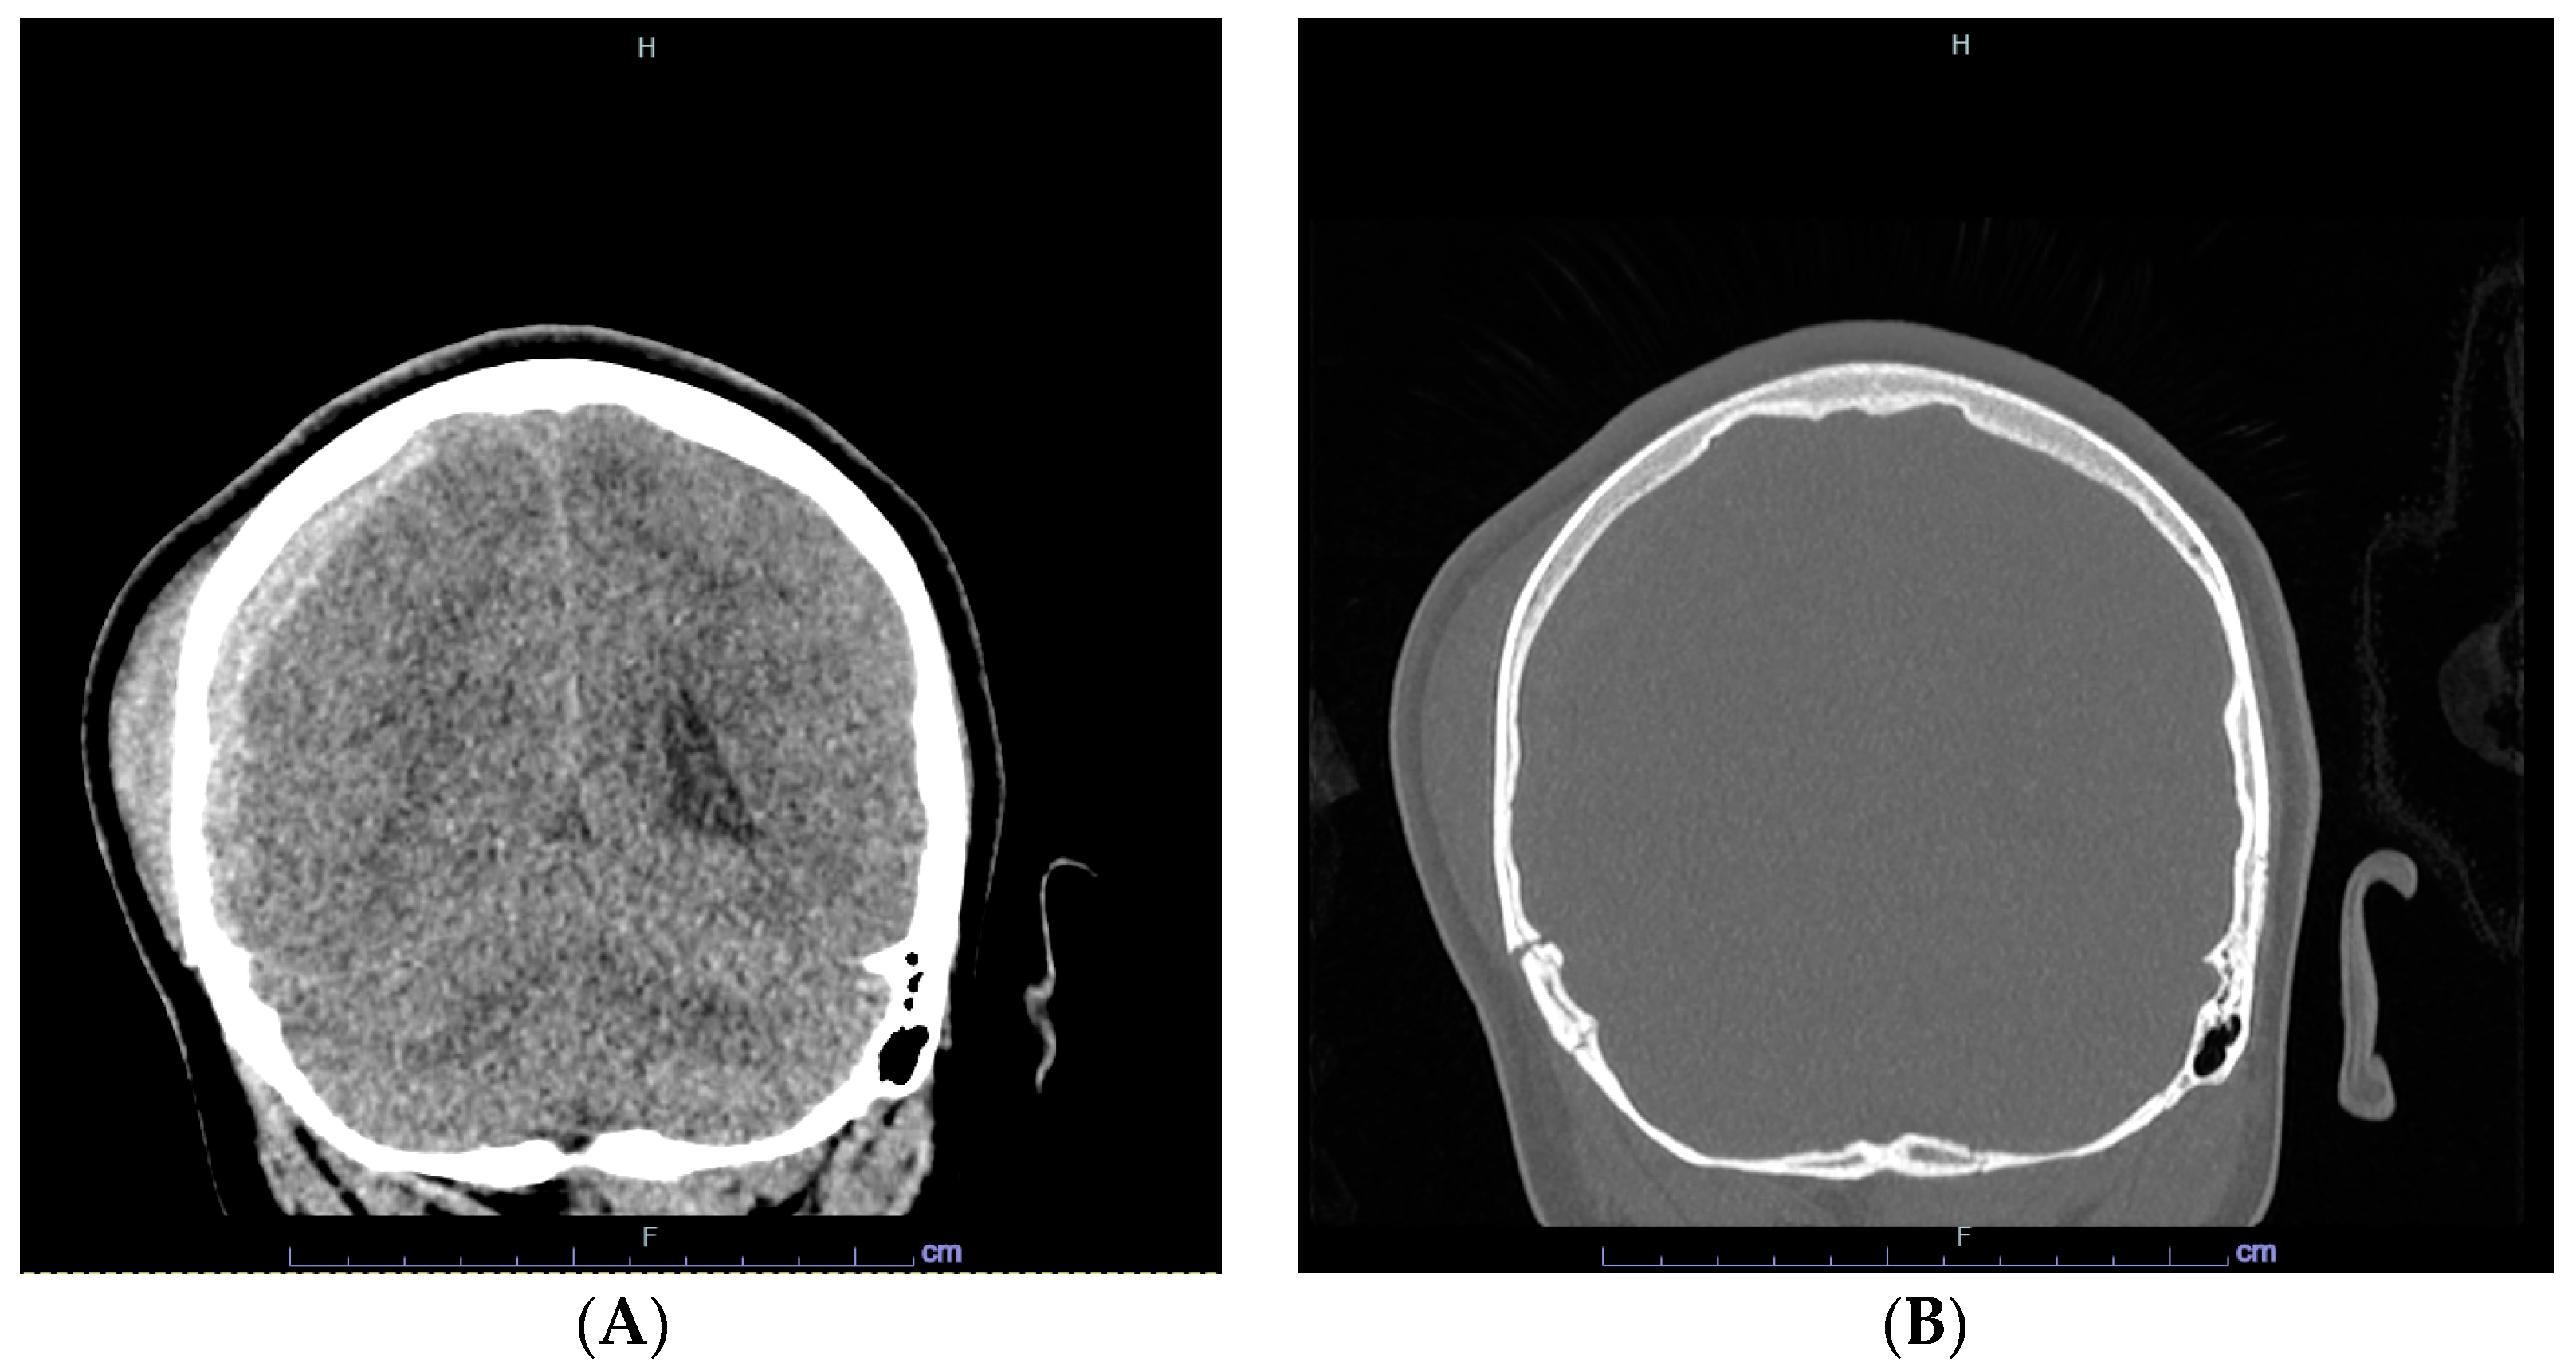

2. Case